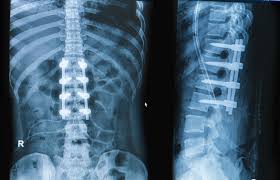

Spine surgery becomes necessary when conservative treatments fail to control symptoms. Common conditions include herniated discs, degenerative disc disease, spinal stenosis, spondylolisthesis, scoliosis, spinal fractures, and nerve compression disorders. These conditions often cause chronic pain, numbness, weakness, and restricted movement that interfere with daily life.

Accurate diagnosis forms the foundation of successful spine surgery. Patients undergo comprehensive assessment including physical examination, MRI, CT scans, and nerve studies when required. These investigations help identify the exact cause of pain and neurological symptoms.

Modern spine surgery focuses on minimizing tissue damage while achieving maximum relief. Minimally invasive spine surgery uses smaller incisions, specialized instruments, and advanced imaging guidance. These techniques reduce muscle injury, blood loss, and post-operative pain.

Varunam Super Speciality Hospital offers advanced spine surgery solutions using modern operation theatres and precision-guided technology. Surgeons focus on nerve decompression, spinal stabilization, and alignment correction based on individual patient needs.